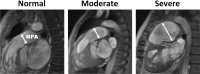

Pulmonary arterial hypertension (PAH) is characterized by elevated pulmonary artery pressure (PAP), altered pulmonary artery (PA) hemodynamics, and vessel wall characteristics that affect the right ventricular (RV) function. Magnetic resonance imaging (MRI) has recently been considered in PAH and has shown promising results for estimating PAP, measuring PA hemodynamic parameters, assessing PA vessel wall stiffness, and evaluating RV global and regional functions. In this article, we review various MRI techniques and image analysis methods for evaluating PAH, with an emphasis on the resulting images and how they are interpreted for both qualitatively and quantitatively assessing the PA and RV conditions.